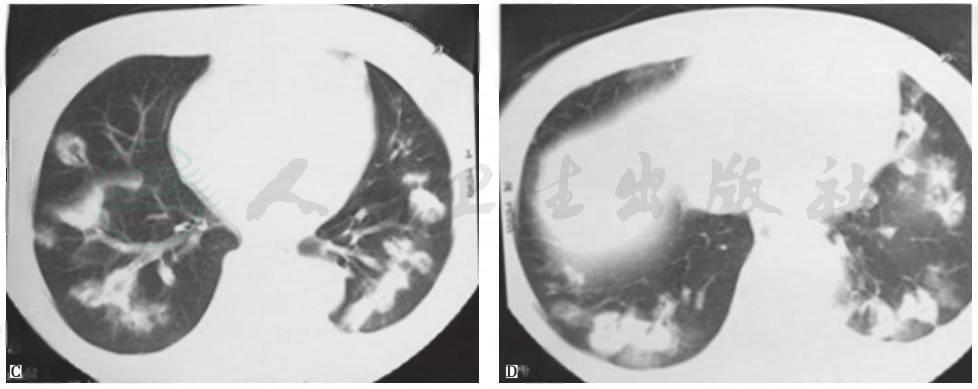

肉芽肿性多血管炎(GPA):既往称为韦格纳肉芽肿,是一种坏死性肉芽肿性血管炎,属于自身免疫性疾病。该病主要侵犯上、下呼吸道和肾脏,通常以鼻黏膜和肺组织的局灶性肉芽肿性炎症为开始,继而进展为血管的弥漫性坏死性肉芽肿性炎症。临床常表现为鼻和鼻旁窦炎、肺病变和进行性肾衰竭,还可累及关节、眼、皮肤、心脏、神经系统及耳等。侵犯肺部时影像学表现可有多样性、多发性及多变性等特点(图6)。本例患者虽有蛋白尿的肾脏损害表现,但临床病程及症状与GPA相距甚远,故考虑GPA可能性不大。

图6韦格纳肉芽肿胸部CT表现

女性患者,21岁,间断咳嗽2个月,诊断为韦格纳肉芽肿。胸部CT可见双肺多发结节影伴空洞形成,各结节影与血管关系密切

胸部CT:两肺见散在多个片状、花环状高密度影,反晕征,部分密度不均,边缘尚清,部分相互融合,大部分可见含气支气管征(图7)。

图7入院后胸部CT表现(发病第50天)

患者入院后所做系列检查显示:①肿瘤标志物及大便检查均阴性,结合临床表现,基本上可排除胃肠道肿瘤肺转移;②虽然抗核抗体为1∶100,但其余自身抗体均阴性,结合临床表现,暂不考虑风湿免疫病;③胸部CT提示病变进一步加重;④常规病原学检查均阴性。因此,不排除曲霉菌感染的可能。但患者应用伊曲康唑治疗10天后,复查胸部CT(图8)提示病情进一步加重,且静息状态下动脉血气呈现低氧血症(FiO2 33%,PaO2 64mmHg)。由此推测,本病例可能是由一些非感染非肿瘤性疾病引起。

图8入院后胸部CT表现(发病第58天)

胸部CT显示,与发病第50天时(图7)相比,双肺原有病灶进一步加重,并出现右侧少量胸腔积液